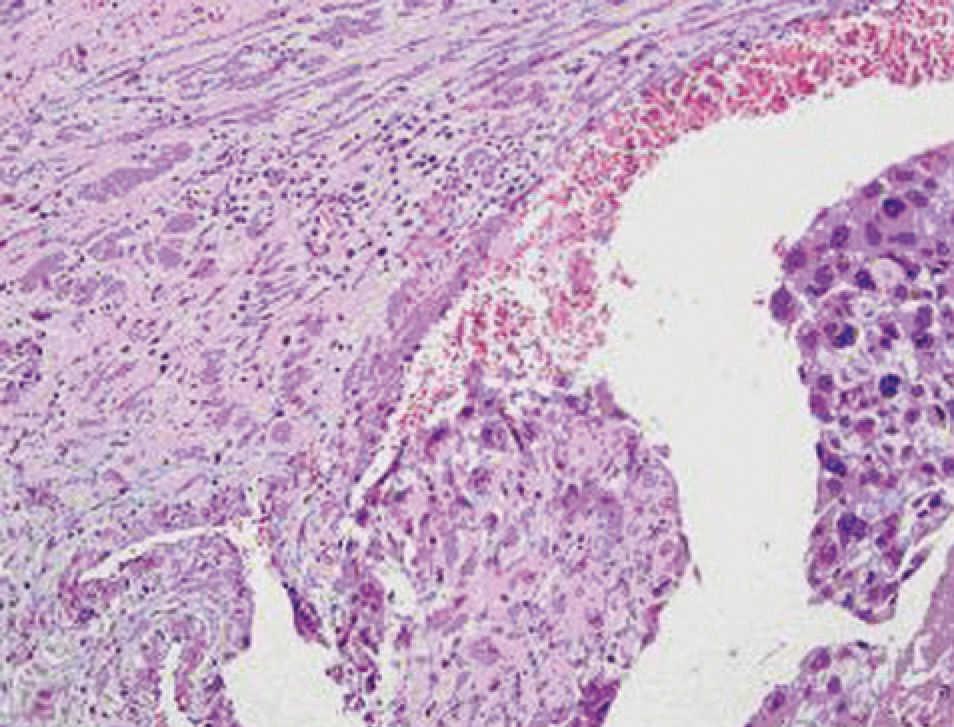

La capa miometrial del útero está compuesta de haces de fibras musculares lisas rodeadas por tejido conjuntivo. La célula del músculo liso uterino no se diferencia terminalmente y, por tanto,…